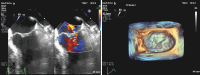

Near complete resolution of nonbacterial thrombotic endocarditis in a patient with antiphospholipid antibody syndrome